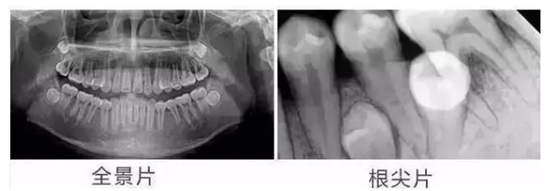

全景片:全景片可以显示全口牙齿的排列情况,以及上下颌骨的结构和形态。它常用于评估牙齿的拥挤程度、判断是否需要正畸治疗等,还可以清晰显示牙冠,牙颈,牙根以及与上下颌骨之间的关系,并对颌骨周围疾病的诊断提供准确有效的帮助。

根尖片:根尖片主要聚焦于单个牙齿及其周围的牙槽骨和牙周组织。它对于诊断牙髓炎、根尖周炎等牙齿内部疾病具有重要意义。